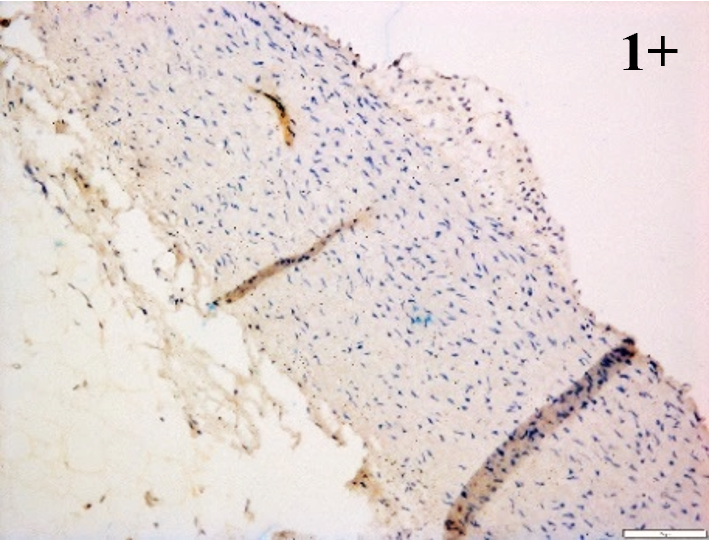

Immunoreactions of ICAM-1, VCAM-1, e-selectin, IL-6, IL-8, NF-

According to the percentage endothelial staining of cells, semi-quantitative

scores were applied. Score: 0 (negative); 1+ (1–10% positive cells); 2+

(11–25% positive cells) and 3+ (

Medium to high expressions of adhesion molecules, such as ICAM-1, VCAM-1 and

e-selectin were observed in the aortas of rabbits fed with HCD. This represents

the initiation of the lesion stage, where the endothelial cells have been

stimulated by the ox-LDL to express the adhesion molecules, which could lead to

the recruitment of monocytes and transmigrate into the intima by diapedesis as

well as differentiate into pro-atherogenic macrophages [47]. An increased

expression of pro-inflammatory biomarkers, such as IL-6, IL-8 and NF-